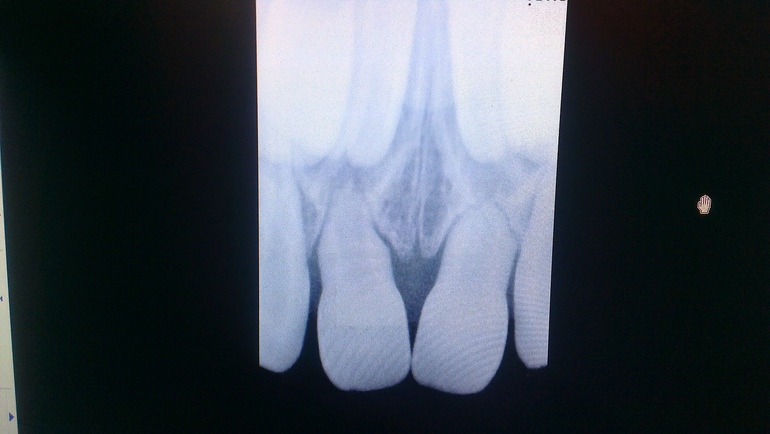

Здравствуйте.На снимке вижу процессы физиологической смены. Несколько смущает правый центральный резец... Но удаления бы не советовала. ВОзможно принудительное рассшатывание.А нижние резцы уже поменялись?

Ну и правильно тогда сделали! Хоть, конечно, и шатать-то недолго бы пришлось... Но раз беспокоили.Удар мог спровоцировать ускорение рассасывания корней.